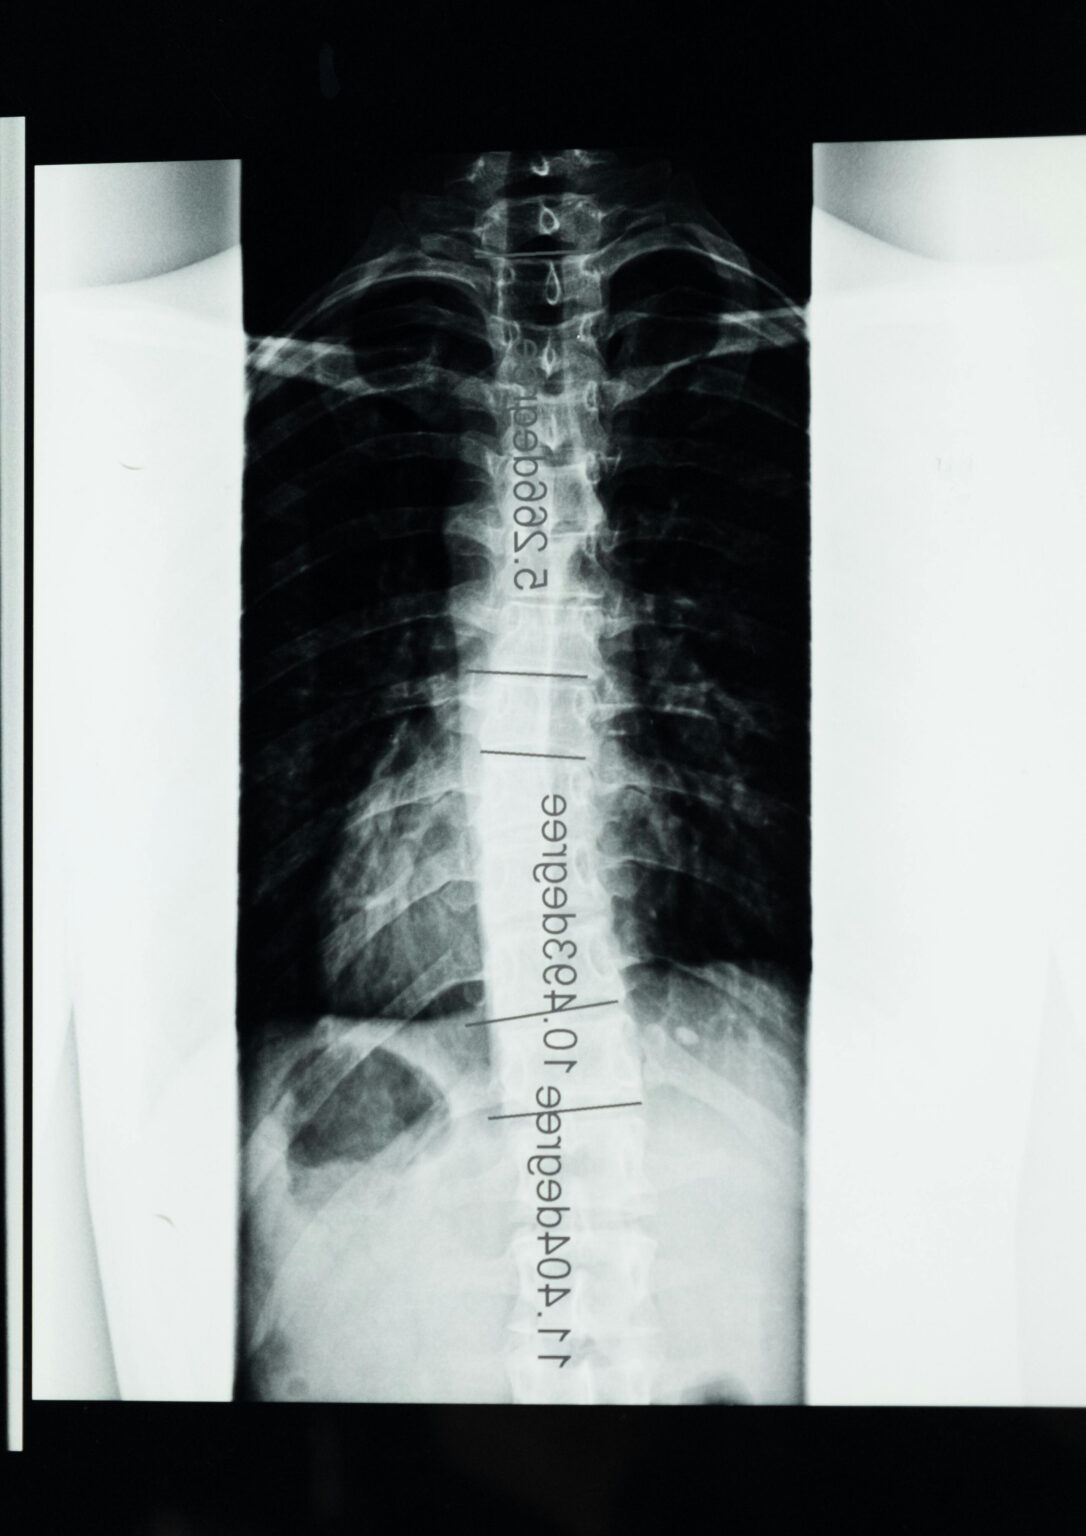

Spinal fusion surgery is a procedure that permanently joins two or more vertebrae (the individual small bones that stack together to form your backbone) to eliminate movement between them. By stabilising the affected segment of the spine, the surgery aims to reduce pain caused by abnormal motion and prevent further damage to surrounding spinal structures.

During the procedure, the neurosurgeon places bone graft material between the affected vertebrae. This graft may come from your own bone, a donor source, or a synthetic substitute. Over time, the bone graft heals and fuses the vertebrae into a single solid unit, providing long-term stability to the spine.